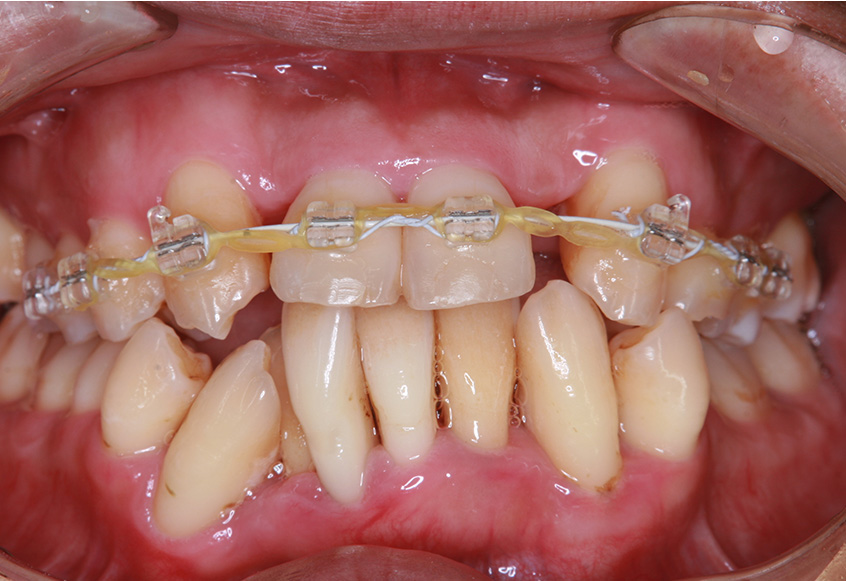

治療開始後3ヵ月経過すると、前歯の隙間や全体の乱れが減ってきました。口笛が吹けるようになったとのことです。

最初のお口の中 治療開始3ヵ月後

6ヵ月経過すると、矯正治療を終了し、前歯に被せ物の治療を行いました。

最初のお口の中 2025/3/22

被せ物装着

| 矯正装置 | 矯正ブラケットとワイヤー |

| 治療内容 | 上顎側切歯を2本抜歯した後、上顎の歯にブラケットを装着し、ワイヤー、矯正用ゴムで歯の移動を行いました。その後、被せ物の治療を行って治療を終了しています。 |